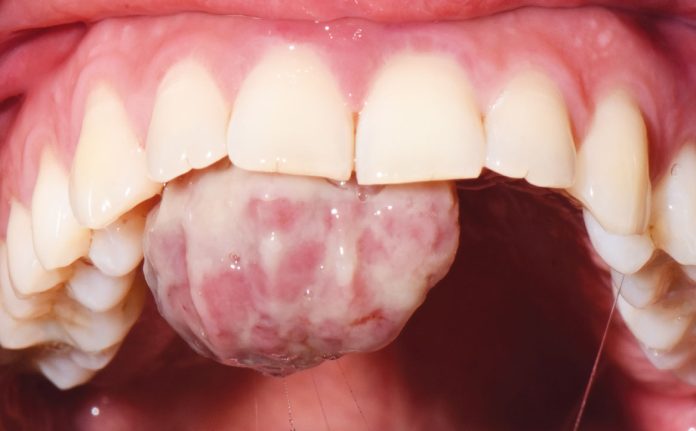

Una donna di 27 anni si è recata presso il Dipartimento di Odontoiatria e Protesi Dentaria dell’Ospedale IRCCS San Raffaele di Milano, diretto dal professor E. F. Gherlone, a causa di una lesione presente sul palato. La paziente, in prima istanza, in seguito a un questionario anamnestico, dichiara di essere al terzo trimestre di gravidanza. Successivamente, all’esame intra-orale è stata riscontrata la presenza di una lesione sessile a livello del palato, osservabile in figura 1 e 2. La diagnosi presuntiva è quella di granuloma piogenico, da confermare attraverso l’esame istopatologico.

La lesione di circa 2 cm, fissata in formalina al 10% tamponata, è stata inviata al reparto di Istologia e Anatomia Patologica dell’IRCCS Ospedale San Raffaele al fine di eseguire l’analisi istopatologica.